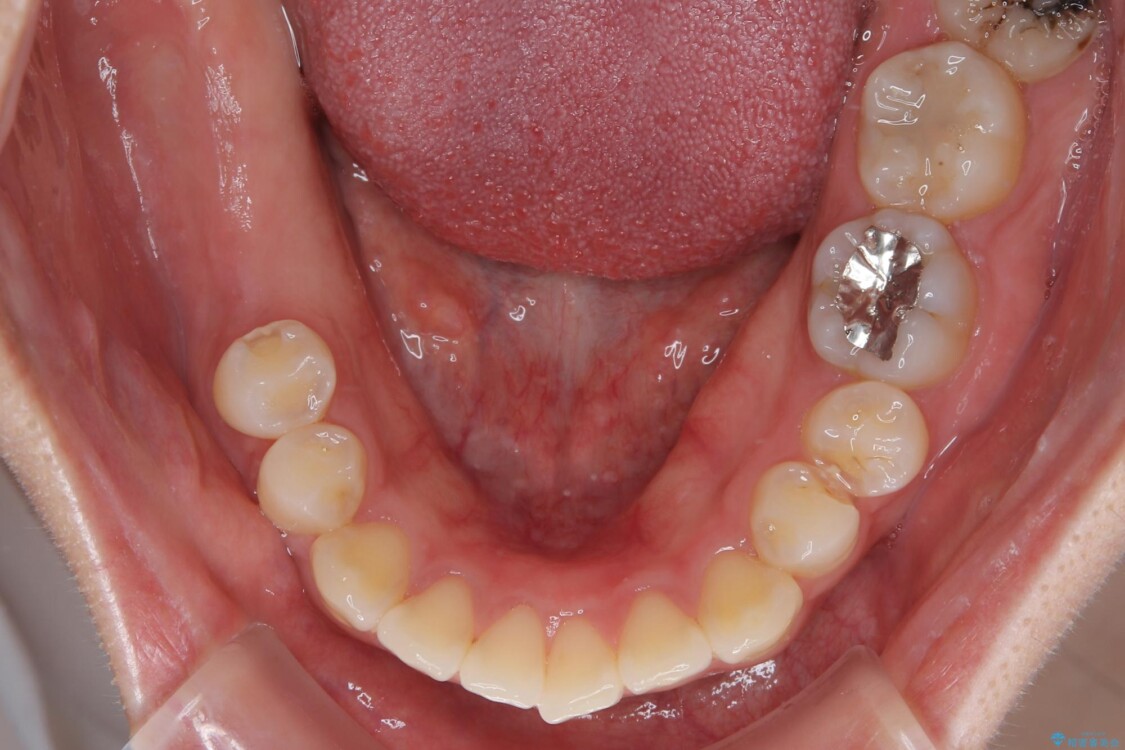

「1年前に抜歯した右下の奥歯にインプラントを入れたい」とのことで来院されました。

インプラント希望部位は右下第一大臼歯と第二大臼歯です。

しかし、噛み合わせの相手である右上の第二大臼歯が、長期間噛み合う歯がなかった影響で**挺出(歯が下に伸びてくる状態)してしまっており、このままではインプラントを埋入して被せもの(上部構造)を入れるためのスペースが不足している状態でした。

• 挺出歯を圧下してスペースを確保!目立たない部分矯正で下顎大臼歯にインプラント治療を実現 治療前画像